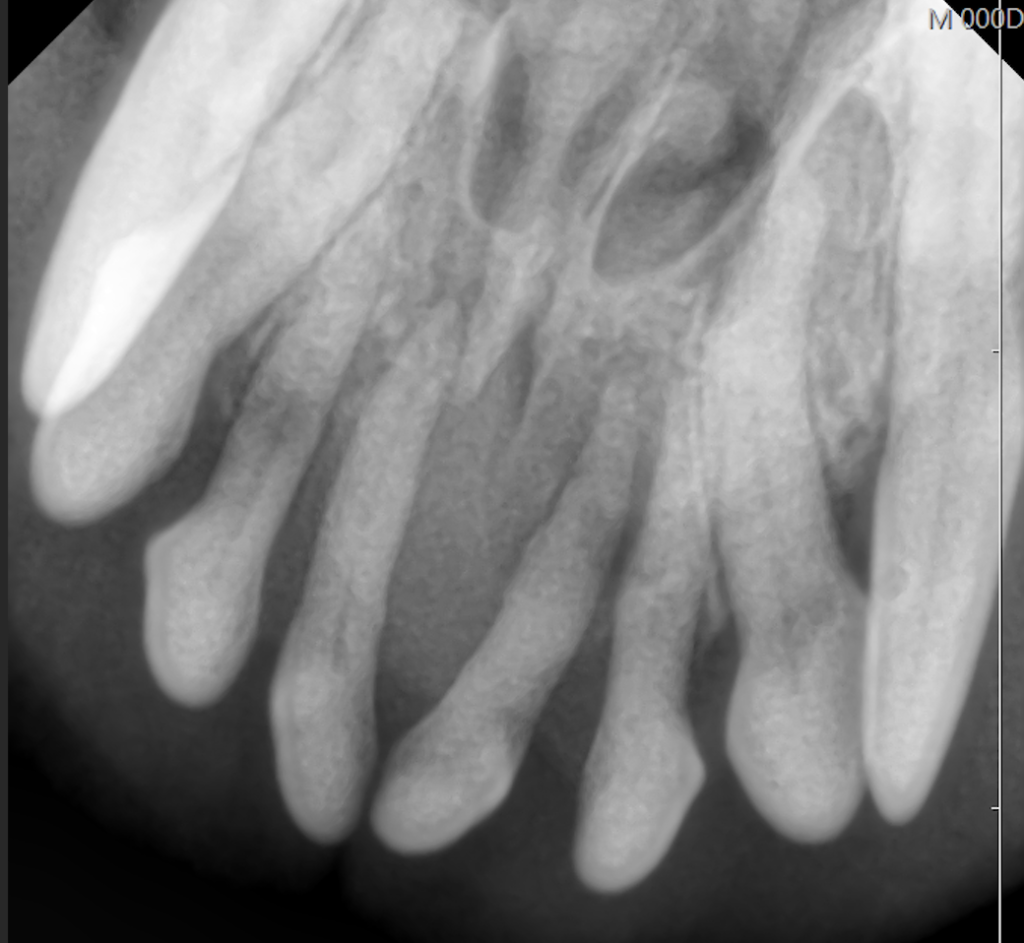

こちらの写真の症例は口臭が気になるという主訴で来院されました。

左右上顎の第一切歯の歯肉が後退しています。

全身麻酔下での精査を行い、歯科レントゲン検査にて歯槽骨の融解が認められ、重度歯周病と診断しました。

小型犬の切歯は温存することが非常に難しく、この子は抜歯処置となりました。